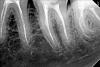

zubiki Опубликовано 4 июля, 2013 Автор Поделиться Опубликовано 4 июля, 2013 И еще отправляю еще один снимок, сделанный в процессе перелечивания. Есть ли там фрагмент инструмента? Ссылка на комментарий

samsonov Опубликовано 4 июля, 2013 Поделиться Опубликовано 4 июля, 2013 По представленным изображениям не очень высокого качества,скорее, отломка нет,чем наоборот. Ссылка на комментарий

АнтонТЛТ Опубликовано 4 июля, 2013 Поделиться Опубликовано 4 июля, 2013 +1 на счет инструмента сложно сказать, плохое качество снимков. Пломбировка действительно так себе. Финальный снимок перелечивания есть? Ссылка на комментарий